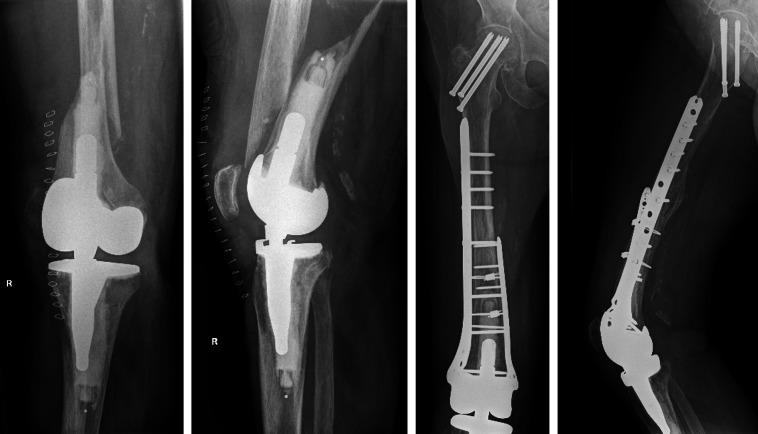

与单钢板固定和股骨远端关节成形术相比,双钢板固定是治疗人工关节周围股骨远端骨折的一种合适选择。

Double plating is a suitable option for periprosthetic distal femur fracture compared to single plate fixation and distal femoral arthroplasty.

The purpose of this study was to compare reoperation and revision rates of double plating (DP), single plating using a lateral locking plate (SP), or distal femoral arthroplasty (DFA) for the treatment of periprosthetic distal femur fractures (PDFFs).

A total of 111 PDFFs (111 patients, median age 82 years (interquartile range (IQR) 75 to 88), 86% female) with 32 (29%) Su classification 1, 37 (34%) Su 2, and 40 (37%) Su 3 fractures were included. The median follow-up was 2.5 years (IQR 1.2 to 5.0). DP, SP, and DFA were used in 15, 66, and 30 patients, respectively. Compared to SP, patients treated with DP were more likely to have metaphyseal comminution (47% vs 14%; p = 0.009), to be low fractures (47% vs 11%; p = 0.009), and to be anatomically reduced (100% vs 71%; p = 0.030). Patients selected for DFA displayed comparable amounts of medial/metaphyseal comminution as those who underwent DP. At a minimum follow-up of two years, revision surgery for failure was performed in 11 (9.9%) cases at a median of five months (IQR 2 to 9): 0 DP patients (0%), 9 SP (14%), and 2 DFA (6.7%) (p = 0.249).

CONCLUSION

Using a strategy of DP fixation in fractures, where the fracture was low but there was enough distal bone to accommodate locking screws, and where there is metaphyseal comminution, resulted in equivalent survival free from revision or reoperation compared to DFA and SP fixation.

本研究旨在比较双钢板固定(DP)、使用外侧锁定钢板的单钢板固定(SP)或股骨远端关节成形术(DFA)治疗股骨假体周围远端骨折(PDFF)的再次手术率和翻修率。

共纳入111例PDFF(111例患者,中位年龄82岁(四分位间距(IQR)75至88岁),86%为女性),其中32例(29%)为苏(Su)分类1型骨折,37例(34%)为Su 2型骨折,40例(37%)为Su 3型骨折。中位随访时间为2.5年(IQR 1.2至5.0)。分别有15例、66例和30例患者使用了DP、SP和DFA。与SP相比,接受DP治疗的患者更易出现干骺端粉碎(47%对14%;p = 0.009)、低位骨折(47%对11%;p = 0.009)以及解剖复位(100%对71%;p = 0.030)。选择DFA治疗的患者其内侧/干骺端粉碎程度与接受DP治疗的患者相当。在至少两年的随访中,11例(9.9%)患者因失败接受了翻修手术,中位时间为5个月(IQR 2至9):0例DP患者(0%)、9例SP患者(14%)和2例DFA患者(6.7%)(p = 0.249)。

结论

对于骨折位置低但有足够远侧骨来容纳锁定螺钉且存在干骺端粉碎的骨折,采用DP固定策略与DFA和SP固定相比,在无需翻修或再次手术方面具有相同的生存率。